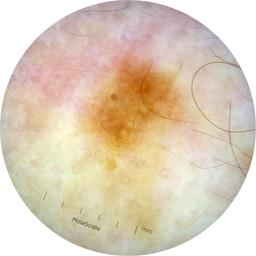

ISIC_9472333

Information

Dimensions

2057 x 2057

acquisition_day 230

age_approx 65

anatom_site_1 Trunk

anatom_site_2 Anterior trunk

anatom_site_general anterior torso

diagnosis_1 Benign

diagnosis_confirm_type single image expert consensus

image_type dermoscopic